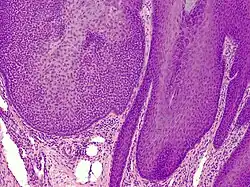

Trichilemmoma (also known as "tricholemmoma"[1]) is a benign cutaneous neoplasm that shows differentiation toward cells of the outer root sheath.[2]: 673 [3] The lesion is often seen in the face and neck region. Multifocal occurrence is associated with Cowden syndrome, in which hamartomatous intestinal polyposis is seen in conjunction with multiple tricholemmoma lesions.